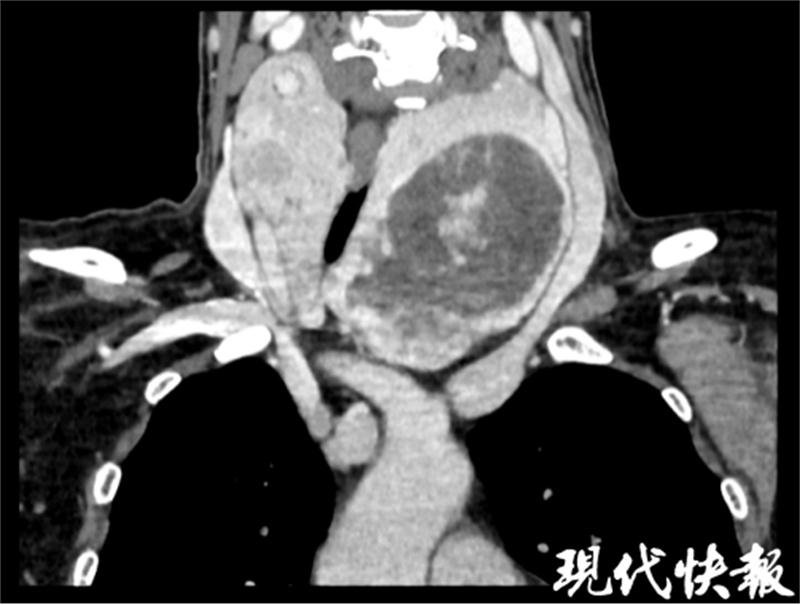

在收治入院完善相关术前检查时发现,李女士胸骨后甲状腺肿巨大,瘤体周围大血管包绕,横切面本应呈圆形的气管已经被压迫成扁扁的椭圆形,且瘤体下方已达到主动脉弓水平,手术风险及难度极大。

△甲状腺肿巨大